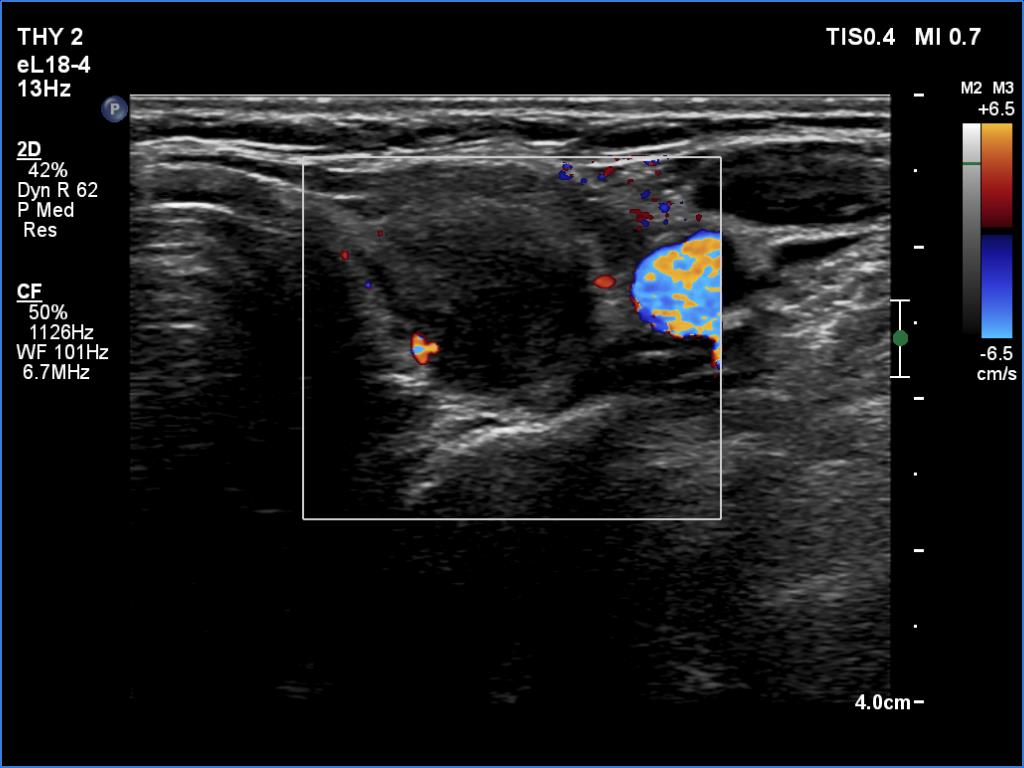

Right lobe, longitudinal scan

Left lobe, transverse scan, color Doppler mode. The lesion is avascular.